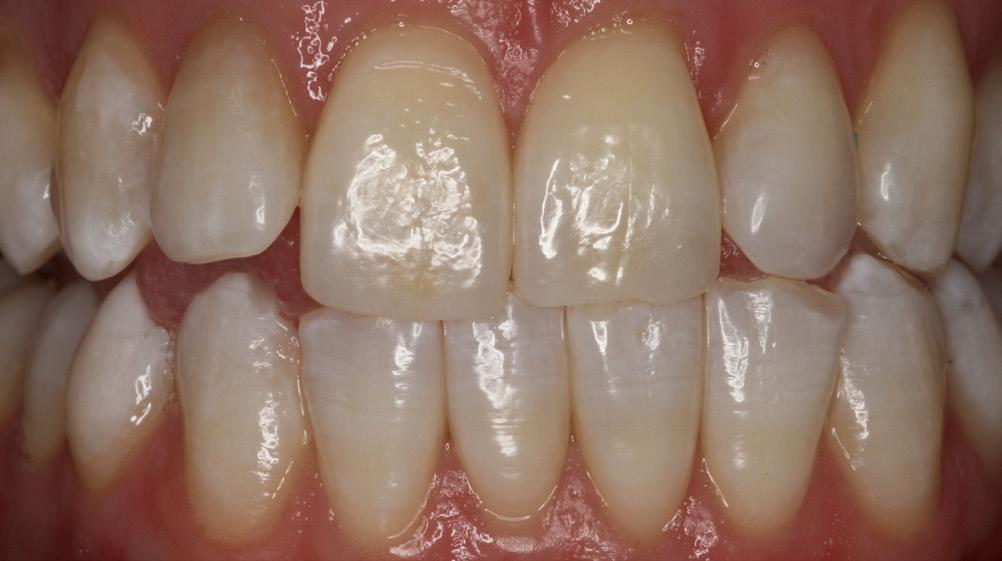

A substantial increase in the apparent length of a tooth, specifically in the anterior labial region, detracts from the esthetic smile. When restoring a Class V decay or abfraction, or perhaps a small gingival recession, an enamel-colored resin is commonly placed at the labial DEJ. Increasing the maxillary central incisor’s vertical aspect (Fig. 1) by a mere 3mm adds 30% to the apparent vertical dimension, significantly altering the cervico-incisal to

mesio-distal (CI:MD) ratio, totally upsetting the esthetic parameters of the smile. (Fig. 2) In situations where there is moderate recession, the visual imbalance is even further impaired. The CI:MD ratio impact is even greater on maxillary laterals and mandibular incisors (average 9.0mm CI). Maxillary and mandibular cuspids (average 10-11mm CI) are often the teeth most affected by gingival recession, and are also highly visible both anteriorly and laterally.

Figure 2: Maxillary incisors apparent length increased by 30%very unnatural and unesthetic

structures to natural dimensions and contours. The restoration should restore lost enamel with enamelshaded composite resin, and receded gingiva with gingival-shaded composite resin. By creating an artificial enamel-gingival junction in composite restorative material, the patient’s esthetics and smile can be restored.